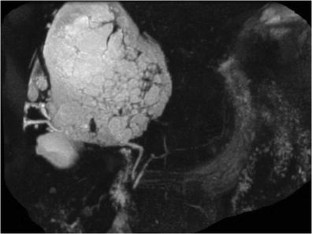

Hepatic Hydatid Cyst: A Rare Cause of Recurrent Pancreatitis

A case of pancreatitis secondary to a hepatic hydatid cyst is illustrated together with its preoperative imaging and intraoperative appearance. Cystobiliary communication is a common complication of large hydatid cysts, and episodes of recurrent pancreatitis resulting from passage of cyst contents down the biliary tract are rarely described. The clinical manifestations, diagnostic workup, and surgical management options of echinococcal-related pancreatitis are discussed, and a review of the literature is provided.

Fig. 1